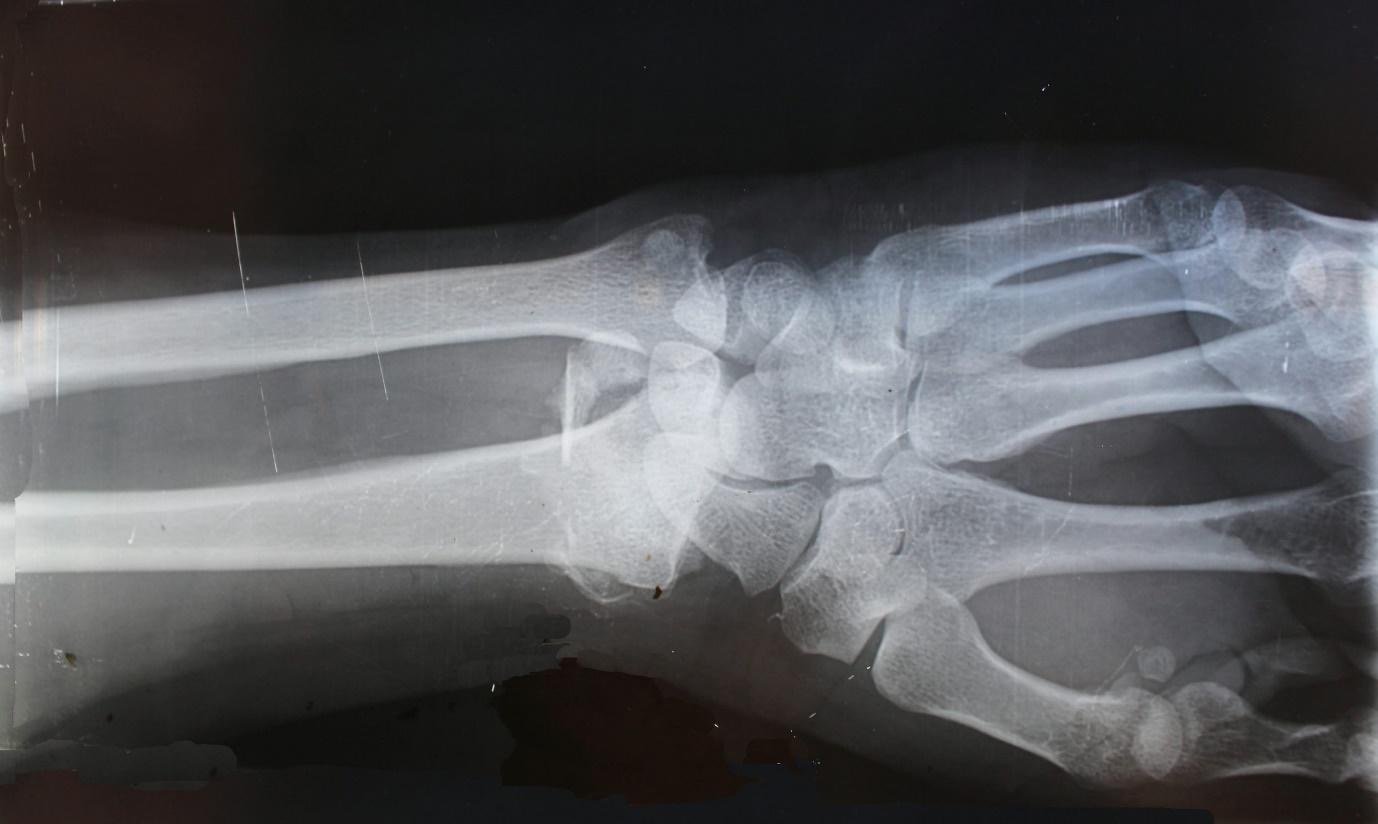

2. Fractures

Fractures are injuries that occur when the stress on a bone exceeds its strength. In gymnastics, the intensity of landings and high-impact skills can cause breaks in the wrist, forearm, ankle, or collarbone. Mistiming in balance beam dismounts and falls from uneven bars can result in fractures fairly quickly. These are usually injuries that require immobilization and, at times, surgery; hence, it takes a long time for the athletes to recover.

In training centers, fractures underscore the importance of regular safety checks, well-maintained equipment, and supervised progressions as gymnasts learn new skills. Even under strict supervision, accidents happen quickly, which makes fractures one of the most concerning injuries to a program.